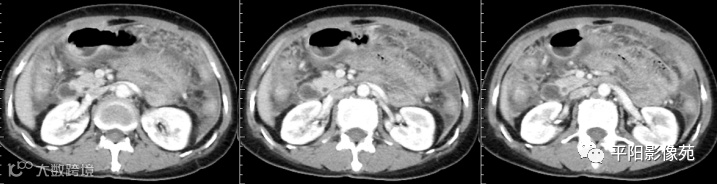

腹部增强 延迟期